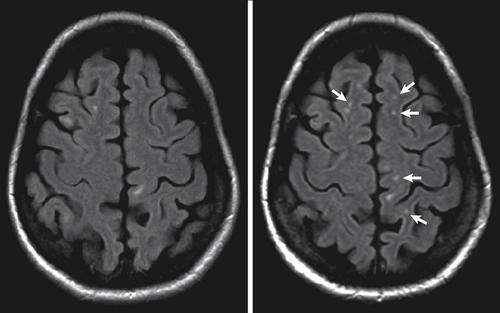

Множественные очаги глиоза

Появление множественных очагов глиоза обусловлено травмами и острыми/хроническими нарушения кровообращения мозга, то есть, сосудистого генеза. По мере развития патологии/заболевания, взывающих гибель нейронов происходит увеличение как количества, так и размера измененных участков.

Возникают преимущественно на фоне выраженного атеросклероза , инсульта , инфаркта мозга , при сдавлении сосудов мозга и в результате возрастных изменений. Множественные очаги глиоза в своем большинстве усиливают клиническую симптоматику основного заболевания и вызывают нарушение функции ЦНС.